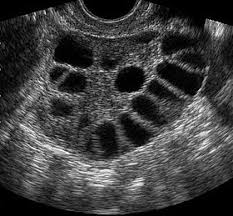

3.Aspetto “policistico” delle ovaie all’ecografia, cioè ovaie con tanti piccoli follicoli (non sono vere cisti e non sono pericolose).

5. Se ho le ovaie policistiche vuol dire che ho la PCOS?

Non sempre. L’aspetto “policistico” delle ovaie può comparire anche in donne sane, soprattutto in età giovane. È solo uno dei criteri diagnostici: serve una valutazione più completa.